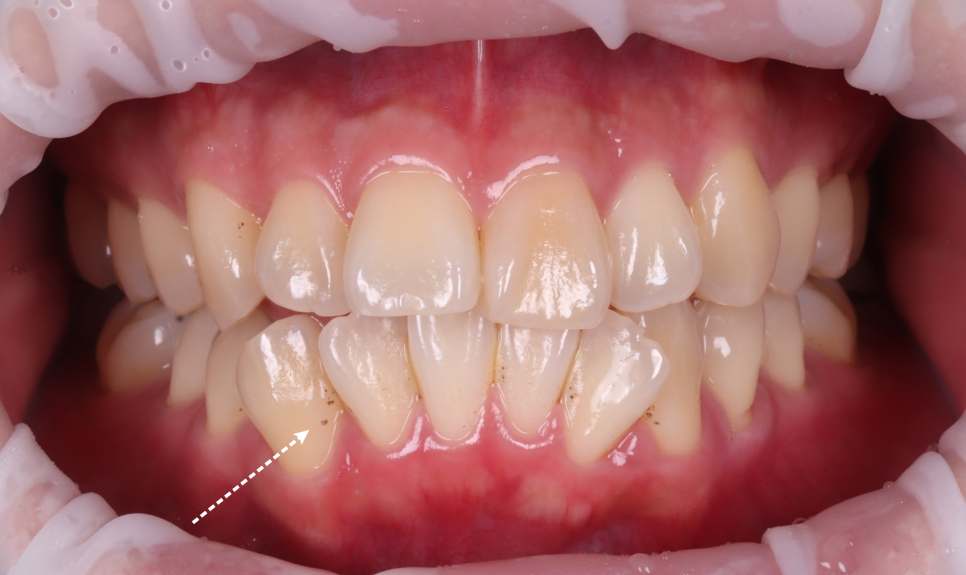

까맣게 착색된 것 때문에 고민이셨던 환자분이 계셨습니다. 스케일링도 주기적으로 받고 계셨고, 양치 습관도 나쁘지 않았지만 늘 앞니와 어금니에 짙은 착색이 남아 있었다고 하셨어요. 제가 착색이 잘 되는 스타일인가 봐요. 서초동치과 이렇게 말씀하셨지만, 저는 그 말이 참 아쉽게 느껴졌습니다...

출처 아카이브 열기까맣게 착색된 것 때문에

고민이셨던 환자분이 계셨습니다.

스케일링도 주기적으로 받고 계셨고,

양치 습관도 나쁘지 않았지만 늘 앞니와

어금니에 짙은 착색이 남아 있었다고 하셨어요.

촬영일 : 250607

이번 환자분도 그랬습니다.

커피를 하루 두세 잔 드시고,

흡연은 하지 않으시지만 치실이나 치간칫솔은

따로 사용하지 않으신다고 하셨어요.

겉으로 보이는 표면에

착색이 도드라진 상태였고,

치아의 안쪽 면, 씹는 면 부근에

브라운 계열의 색소가 고착되어 있었습니다.